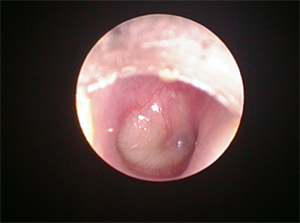

ORL potíže u dětí: Co rodiče často podceňují a proč se vyplatí přijít včas k lékaři

Rýma, bolest ucha, horečka nebo podezření, že dítě hůře slyší. ORL obtíže patří k nejčastějším zdravotním problémům dětského věku a dokážou potrápit nejen malé pacienty, ale i jejich rodiče. Jak poznat, kdy už nejde jen o běžné nachlazení, co funguje jako prevence a kdy je na místě vyhledat odborníka? Odpovídá přednosta ORL kliniky Fakultní nemocnice Plzeň doc. MUDr. David Slouka, Ph.D., MBA.

Téměř každý rodič zná situaci, kdy dítě začne smrkat, přidá se kašel, zvýšená teplota a během noci se objeví silná bolest ucha. Zánět středního ucha (otitida) patří k nejčastějším dětským onemocněním – alespoň jednou ho prodělají tři ze čtyř předškolních dětí.

Velká část akutních zánětů má virový původ a často souvisí s běžnými infekcemi horních cest dýchacích. „Laicky lze říci, že při zánětu středního ucha dochází k přenosu infekce z horních cest dýchacích do oblasti středního ucha. Kvůli neprůchodnosti Eustachovy trubice se zde začne hromadit zánětlivá tekutina, která tlačí na ušní bubínek. U dětí je Eustachova trubice kratší, širší a uložena více horizontálně než u dospělých, a infekce se tak do středouší dostává snáze,“ vysvětluje doc. MUDr. David Slouka, Ph.D., MBA, přednosta ORL kliniky FN Plzeň.

Pokud se za bubínkem vytvoří hnis a dojde k jeho vyklenutí, může být nutná paracentéza – drobný chirurgický zákrok, který dítěti rychle uleví od bolesti.

Foto ilustrační FN Plzeň